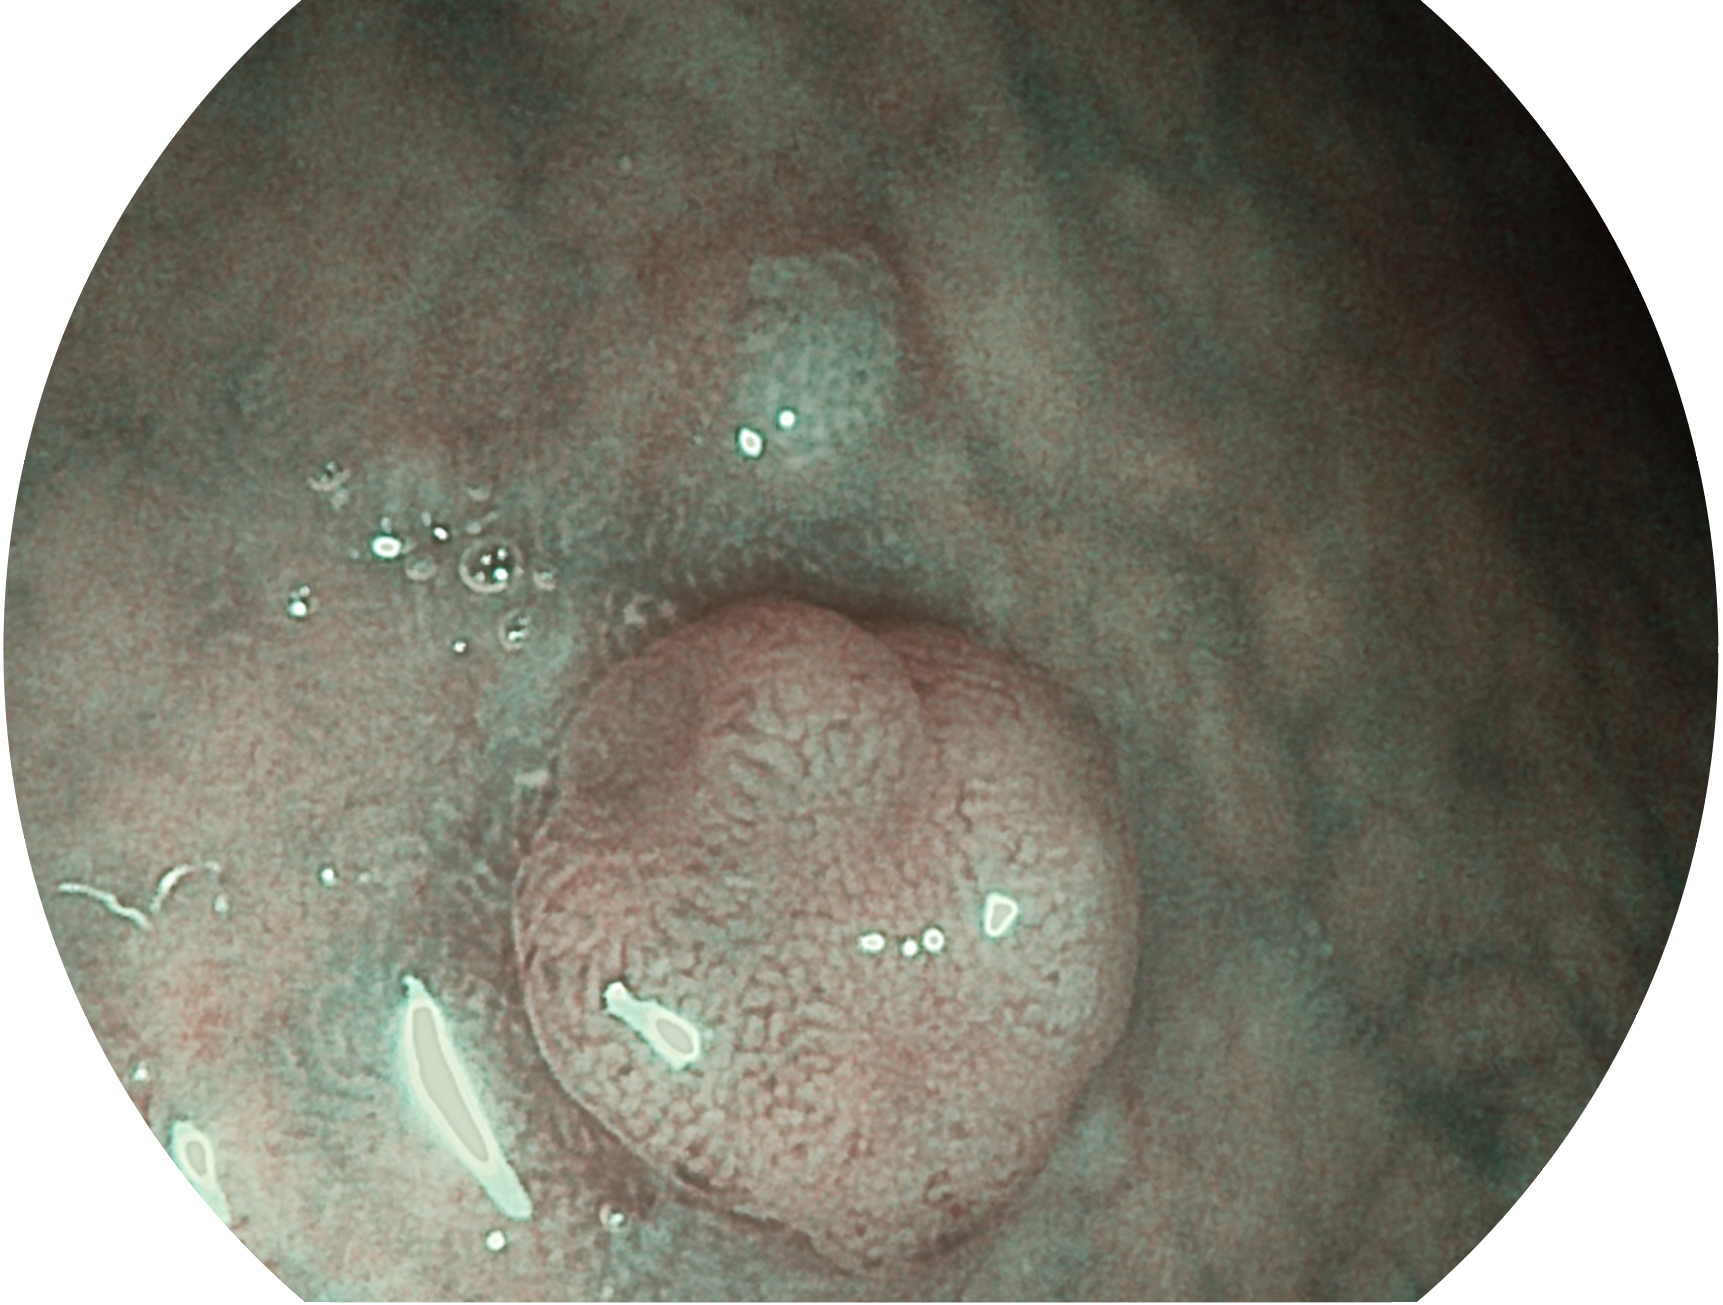

环球UG官网新开发的内镜染色技术,主要是基于多波长LED 光源的开发,VLS-55Q 四波长LED 光源是由四个不同颜色的LED光按照相应照明模式所规定的特定发光比例进行合束后形成,合束后形成的照明光的光谱由红光、绿光、蓝光及蓝紫光这四个不同的波段范围构成。具有更高光谱自由度,通过光谱比例的控制,实现了聚谱成像技术,英文全称为“Spectral Focused Imaging, SFI”,缩写为“SFI”和光电复合染色成像技术,英文全称为“Versatile Intelligent Staining Technology, VIST”,缩写为“VIST”。